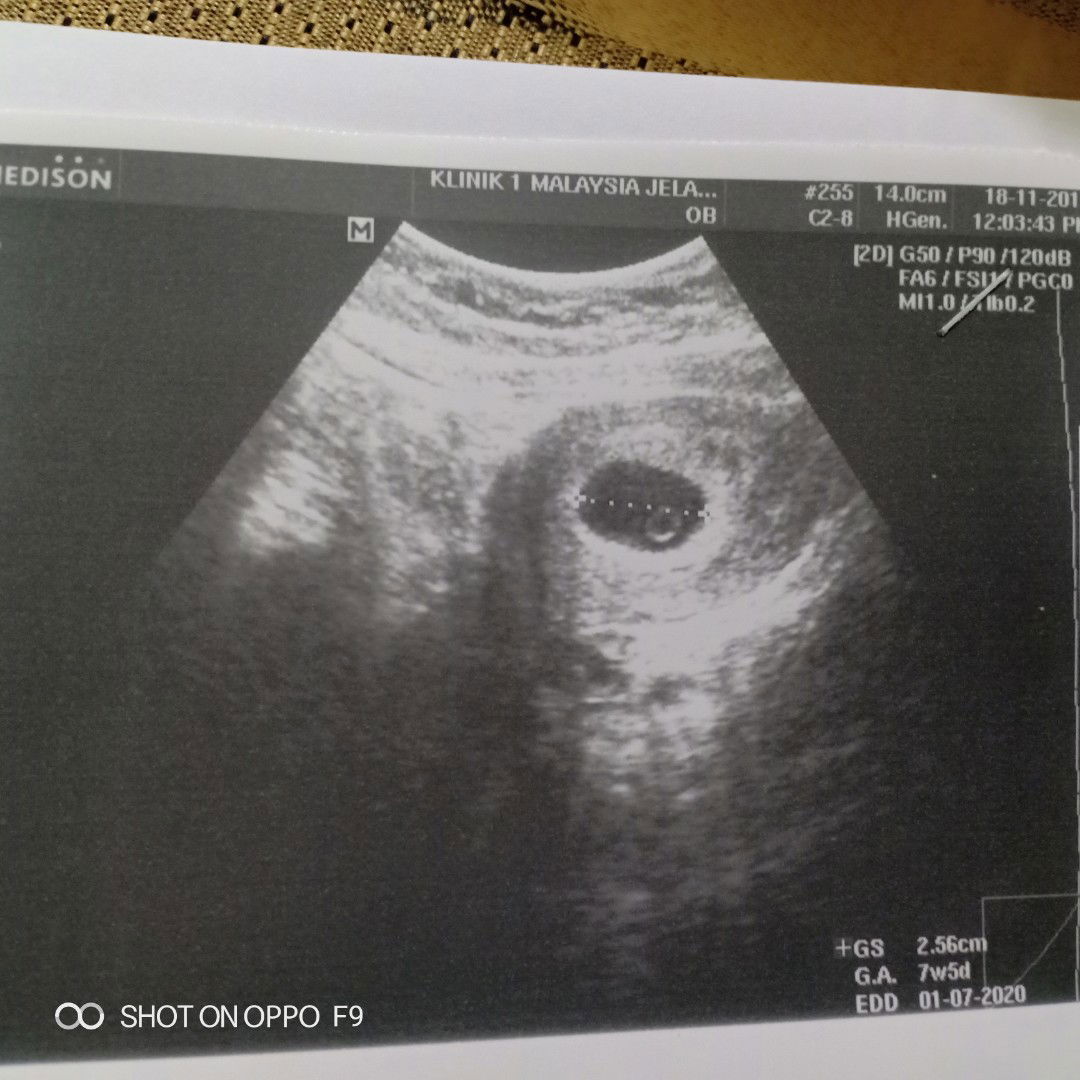

Normal ke kalau kira ikut last period kita dah masuk 10 minggu tapi bila scan doktor kata pelik sbb tak nampak baby, cuma ada kantung je. Kt album scan bru masuk 7 minggu lebih. Ada yang pernah jadi macam ni tak? Saya cuak sebab doktor kata mungkin baby masih kecil atau hanya kantung sahaja ?